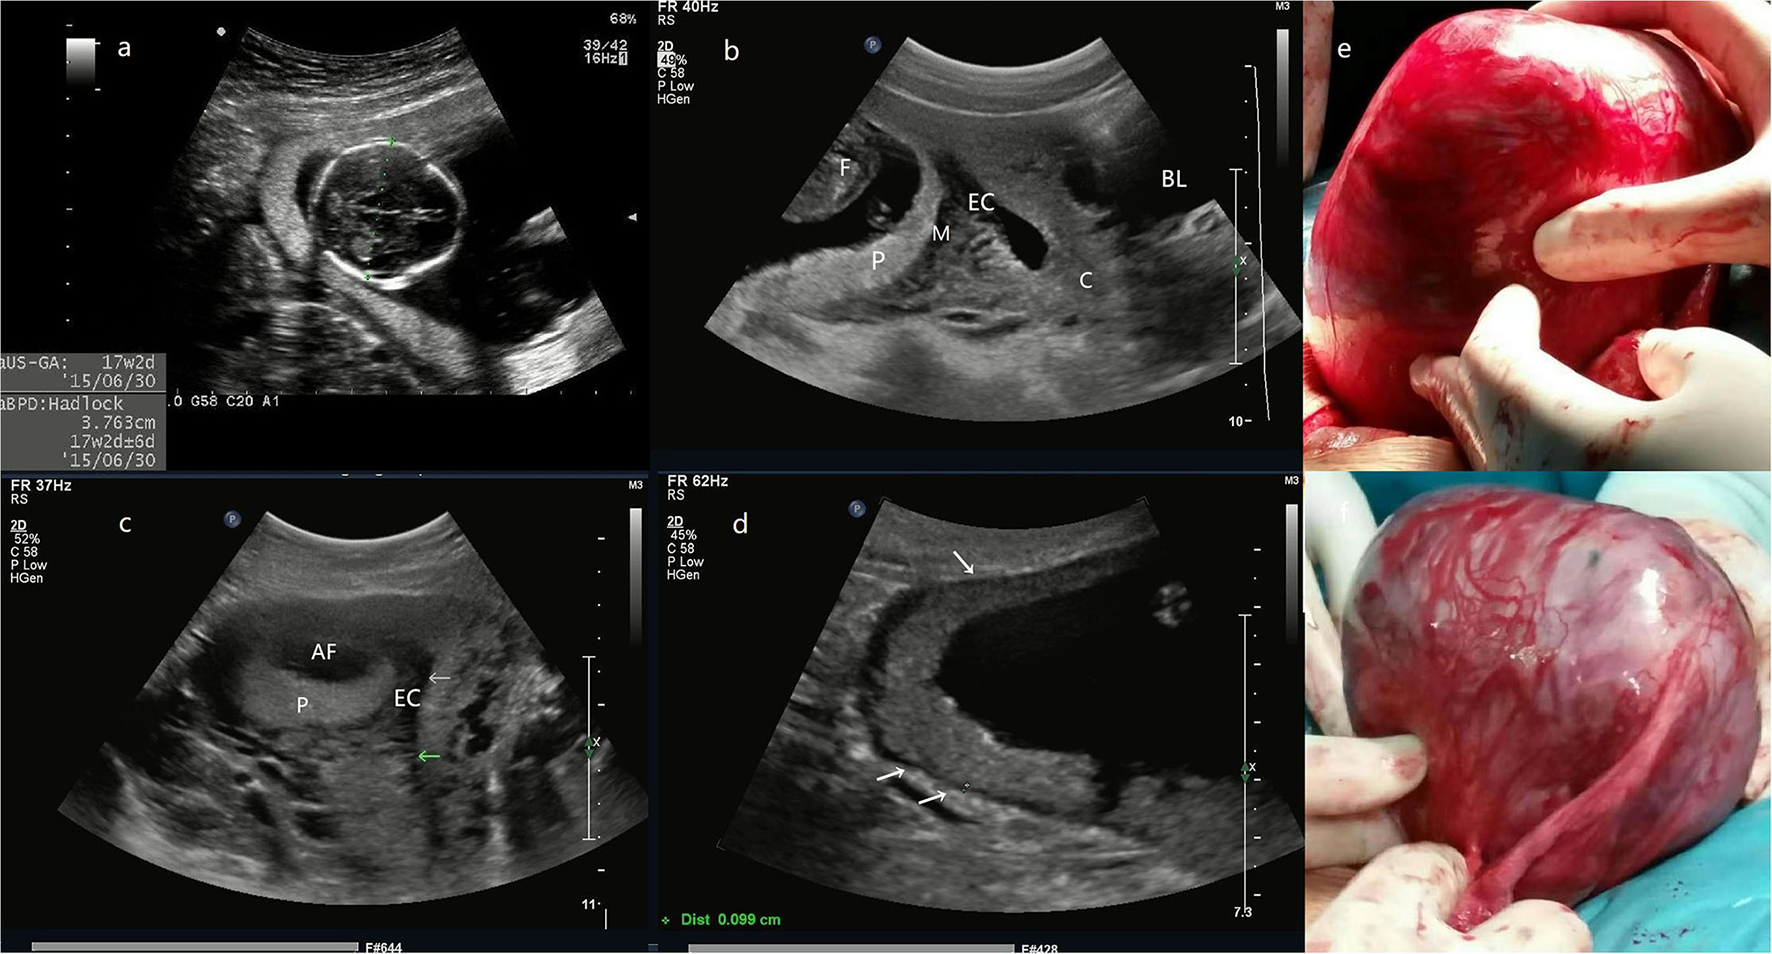

Figure 1

(a) the biparietal diameter of the fetus is 38 mm, the estimated gestational age is 17 weeks and 2 days. (b) The midsagittal section image reveals that the posterior myometrium is between GS and the EC. (c) The transversal section shows that the GS is located in the right posterior wall with a myometrial echo between GS and the EC (arrow). (d) The site of placental attachment covers the entire right posterior wall of the uterus, with a myometrial thickness of 0.9–1.2 mm (arrow). (e) The intraoperative image, an enlarged uterus with a thin wall mass (a size of 14 cm) protrudes at the right posterior wall of the fundus, the fetus, and fetal movement is also palpable. (f) Another photo during the surgery. The entire GS is within the myometrium and does not connect with the uterine cavity even after the removal of the fetus and the placenta (Patient 1, GS, gestational sac; F, fetus; P, placenta; M, myometrium; EC, endometrial cavity; AF, amniotic fluid; C, cervix; BL, bladder).